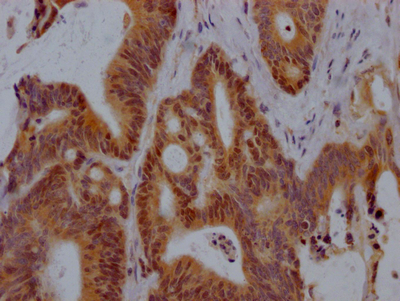

-